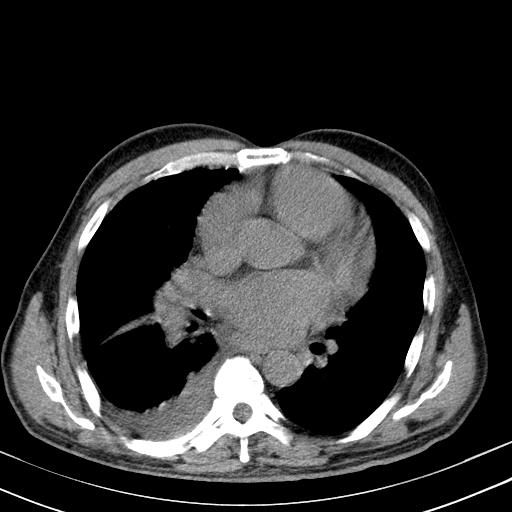

以下是引用zjzjr在2010-3-21 17:39:00的发言:[br]右下中心型肺癌并阻塞性肺炎/不张,纵膈淋巴结肿大,右侧大量胸腔积液,左侧少量胸腔积液

以下是引用zxl51642在2010-3-21 17:06:00的发言:[br]右下中心型肺癌并阻塞性肺炎/不张,纵膈淋巴结肿大,右侧大量胸腔积液,左侧少量胸腔积液,少量腹水。建议纤维支气管镜进一步检查。